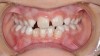

Mouth breathing has also been associated with dental malocclusions in children.2 Zicari and colleagues' analysis of 71, 6- to 12-year-old mouth breathing children revealed a 72.5% incidence of reduced transverse diameter of the maxilla and increased vertical dimension, a 32.5% incidence of cross bite, a 43.7% incidence of skeletal class II malocclusions, and a 90% incidence of atypical swallowing patterns. The results showed a strong correlation between oral breathing and malocclusions, which manifests as both dentoskeletal and functional alterations, leading to a dysfunctional malocclusive pattern (Figure 1 through Figure 3). The study concludes that “this dysfunctional malocclusive pattern makes it clear that the association between oral breathing and dental malocclusions represents a self-perpetuating vicious circle in which it is difficult to establish if the primary alteration is respiratory or maxillofacial. Regardless, the problem needs to be addressed and solved through the close interaction of the pediatrician, otorhinolaryngologist, allergologist, and orthodontist.”

(1.) In children, mouth breathing with low tongue posture can result in narrow maxillary arches, dental crowding, tongue scalloping, and anterior open bites. Images courtesy of Kevin Boyd, DDS, MSc.

Figure 1

(2.) In children, mouth breathing with low tongue posture can result in narrow maxillary arches, dental crowding, tongue scalloping, and anterior open bites. Images courtesy of Kevin Boyd, DDS, MSc.

Figure 2

(3.) In children, mouth breathing with low tongue posture can result in narrow maxillary arches, dental crowding, tongue scalloping, and anterior open bites. Images courtesy of Kevin Boyd, DDS, MSc.

Figure 3